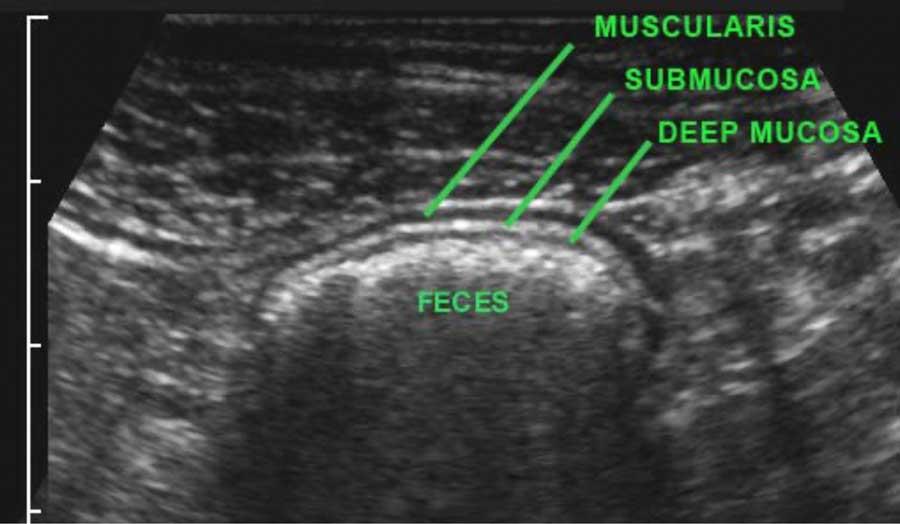

US fingerprint of the normal GI tract

Cấu trúc năm lớp kinh điển của thành ruột trên siêu âm được hiểu rõ nhất khi quan sát thành dạ dày chứa đầy dịch.

Các lớp, bắt đầu từ trong ra ngoài, có cấu trúc tăng âm-giảm âm-tăng âm-giảm âm-tăng âm hoặc trắng-đen-trắng-đen-trắng.

Cấu trúc thành ruột của Mỹ về cơ bản giống nhau từ dạ dày đến trực tràng.

Superficial mucosa

Lớp niêm mạc nông tăng âm rõ rệt, do chất nhầy và các hạt khí rất nhỏ bị giữ lại giữa các nhung mao ruột non.

Nó không thể nhận diện riêng biệt khi hòa lẫn với phân tăng âm, như trong hình ảnh siêu âm đại tràng này.

Lớp thanh mạc trắng bên ngoài chỉ có thể được xác định khi có cổ trướng.

Khi sử dụng đầu dò tần số cao, ba lớp giữa, bao gồm lớp niêm mạc sâu, lớp dưới niêm mạc và lớp cơ (đen-trắng-đen) luôn luôn hiển thị rõ ràng.

Ở bệnh nhân này với tình trạng ứ phân nặng, cấu trúc thành ba lớp chỉ có thể được nhận diện bằng đầu dò 12 MHz.